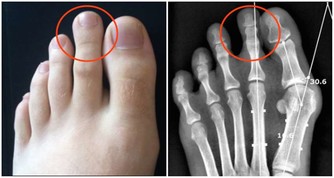

1、水毒 陰毒中最嚴重的就是水毒,一般由腎功能衰弱引起。20歲以上的人應該注意,如果早上起來下眼皮、腳踝浮腫,很有可能就是水濁。想要驅逐水毒,首先要看醫生,檢查腎臟和心臟有無疾病,如果水毒是因腎功能不好導致的,可以服用金匱腎氣丸,通過溫腎來調動機體的氣化能力;如果腎臟和心臟都沒有病,那說明氣血運行不好,需要多運動,飲食上可多吃一些除水濕的絲瓜、冬瓜等。 2、濕毒 濕是水的異常形態,由水轉化而來。體內有濕毒的人,一般表現為舌苔白膩、噁心、不想吃飯等。濕毒主要是因脾氣虛,不能化濕導致的。我們常吃的食物中,豆類最養脾,可以用各種豆子熬成粥喝;還可以用黨參、白朮燉肉吃,有不錯的健脾除濕 升清降濁效果。 3、痰毒